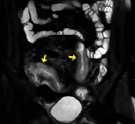

Souhrn: Úvod: Zobrazovací metody mají v diagnostice pacientů s Crohnovou chorobou nezastupitelnou úlohu. V současné době existuje několik skórovacích systémů, jejichž cílem je pomocí předem stanovených parametrů objektivizovat hodnocení zánětlivého postižení střeva. Cílem této práce bylo srovnání nálezu zánětlivého střevního postižení na koloskopii a magnetické rezonanci (MR) při použití skórovacího systému MaRIA. Materiály a metody: Pacienti s Crohnovou chorobou podstoupili v rozmezí do 2 měsíců koloskopii a MR enterografii ve Fakultní nemocnici Brno v letech 2020–2022. Aktivita onemocnění na koloskopii byla hodnocena pomocí SES-CD a Rutgeerts score, na MR pomocí MaRIA skóre (zesílení stěny, její sycení, edém a přítomnost ulcerací). Nálezy z obou zobrazovacích metod byly srovnány, koloskopie byla zvolena zlatým standardem. U každého pacienta bylo analyzováno terminální ileum, tlusté střevo (rozdělené anatomicky na čtyři segmenty) a rektum. Výsledky: V této retrospektivní studii bylo analyzováno 203 střevních segmentů u 43 po sobě jdoucích pacientů (42 % mužů). Senzitivita MR enterografie v hodnocení aktivity střevního zánětu byla 62 %, specificita 94 %. Všechny parametry určující aktivitu zánětu na MR byly signifikantně vyšší u pacientů s aktivitou dle koloskopie a celková hodnota MaRIA skóre byla rovněž vyšší v této skupině (12,76 ± 7,48 vs. 5,27 ± 3,45; p < 0,001). Senzitivita se zvýšila na 90 % při izolované analýze tenkého střeva, při analýze tlustého střeva se naopak snížila na 34 %. Závěr: V naší studii jsme prokázali shodu mezi MR s použitím MaRIA skórovacího systému a koloskopií při hodnocení střevního zánětu u pacientů s Crohnovou chorobou. Klí ová slova: magnetická rezonance – koloskopie – Crohnova choroba – MaRIA

Hodnocení střevního postižení u pacientů s Crohnovou chorobou pomocí MaRIA skórovacího systému

203 střevních segmentů vyšetřeno na MR a koloskopii (17 % tenké střevo, 73 % tlusté střevo, 10 % rektum)

MaRIA = (1,5 × šíře stěny [mm]) + (0,02 × RCE) + (5 × edém stěny) + (10 × ulcerace)

tenké + tlusté střevotenké střevotlusté střevorektum senzitivita 62 %senzitivita 90 %specificita 96 %specificita 89 % specificita 94 %PPV 93 %NPV 86 %NPV 94 %

Parametry na MR: šíře stěny edém stěny sycení stěny (RCE) ulcerace stěny